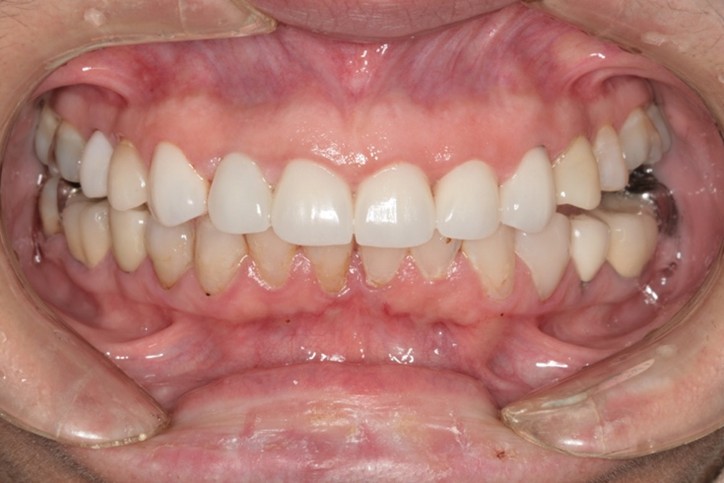

抜歯即時インプラント埋入

| 年代 | 56歳 |

|---|---|

| 性別 | 女性 |

| 治療内容 | 高度齲蝕歯の抜歯と抜歯即時インプラント埋入1本、上顎前歯の審美補綴(ジルコニアセラミック冠)3本 上額前歯1本の抜歯即時インプラント。上顎前歯3歯のジルコニアセラミックによる歯冠補綴 レントゲン診断、CT診断、補綴シミュレーション、血液検査、心電図、サージカルガイド製作、静脈内鎮静法、抜歯、インプラント埋入、暫間補綴、印象・咬合採得、インプラント上部構造装着、ジルコニアセラミック冠装着、メインテナンス |

| 治療期間 | |

| リスク | 術中の不可抗力によるトラブル(出血など)、術後注意事項を守らないことによる疼痛、感染、上部構造装着後口腔内清掃を怠ったことによるインプラント周囲組織の炎症 |

| 副作用 | 治療後の口腔内清掃、及びメインテナンスを怠ったことによるインプラント周囲粘膜炎またはインプラント周囲炎 |

| 費用 | 1,056,000円(税込) (CT撮影診断、血液検査、心電図モニター、補綴シュミュレーション、治療用義歯、サージカルガイド製作、静脈内鎮静法、インプラント埋入、投薬、2次手術、印象・咬合採得、ジルコニアセラミック歯冠補綴、インプラント上部構造などを含む) |